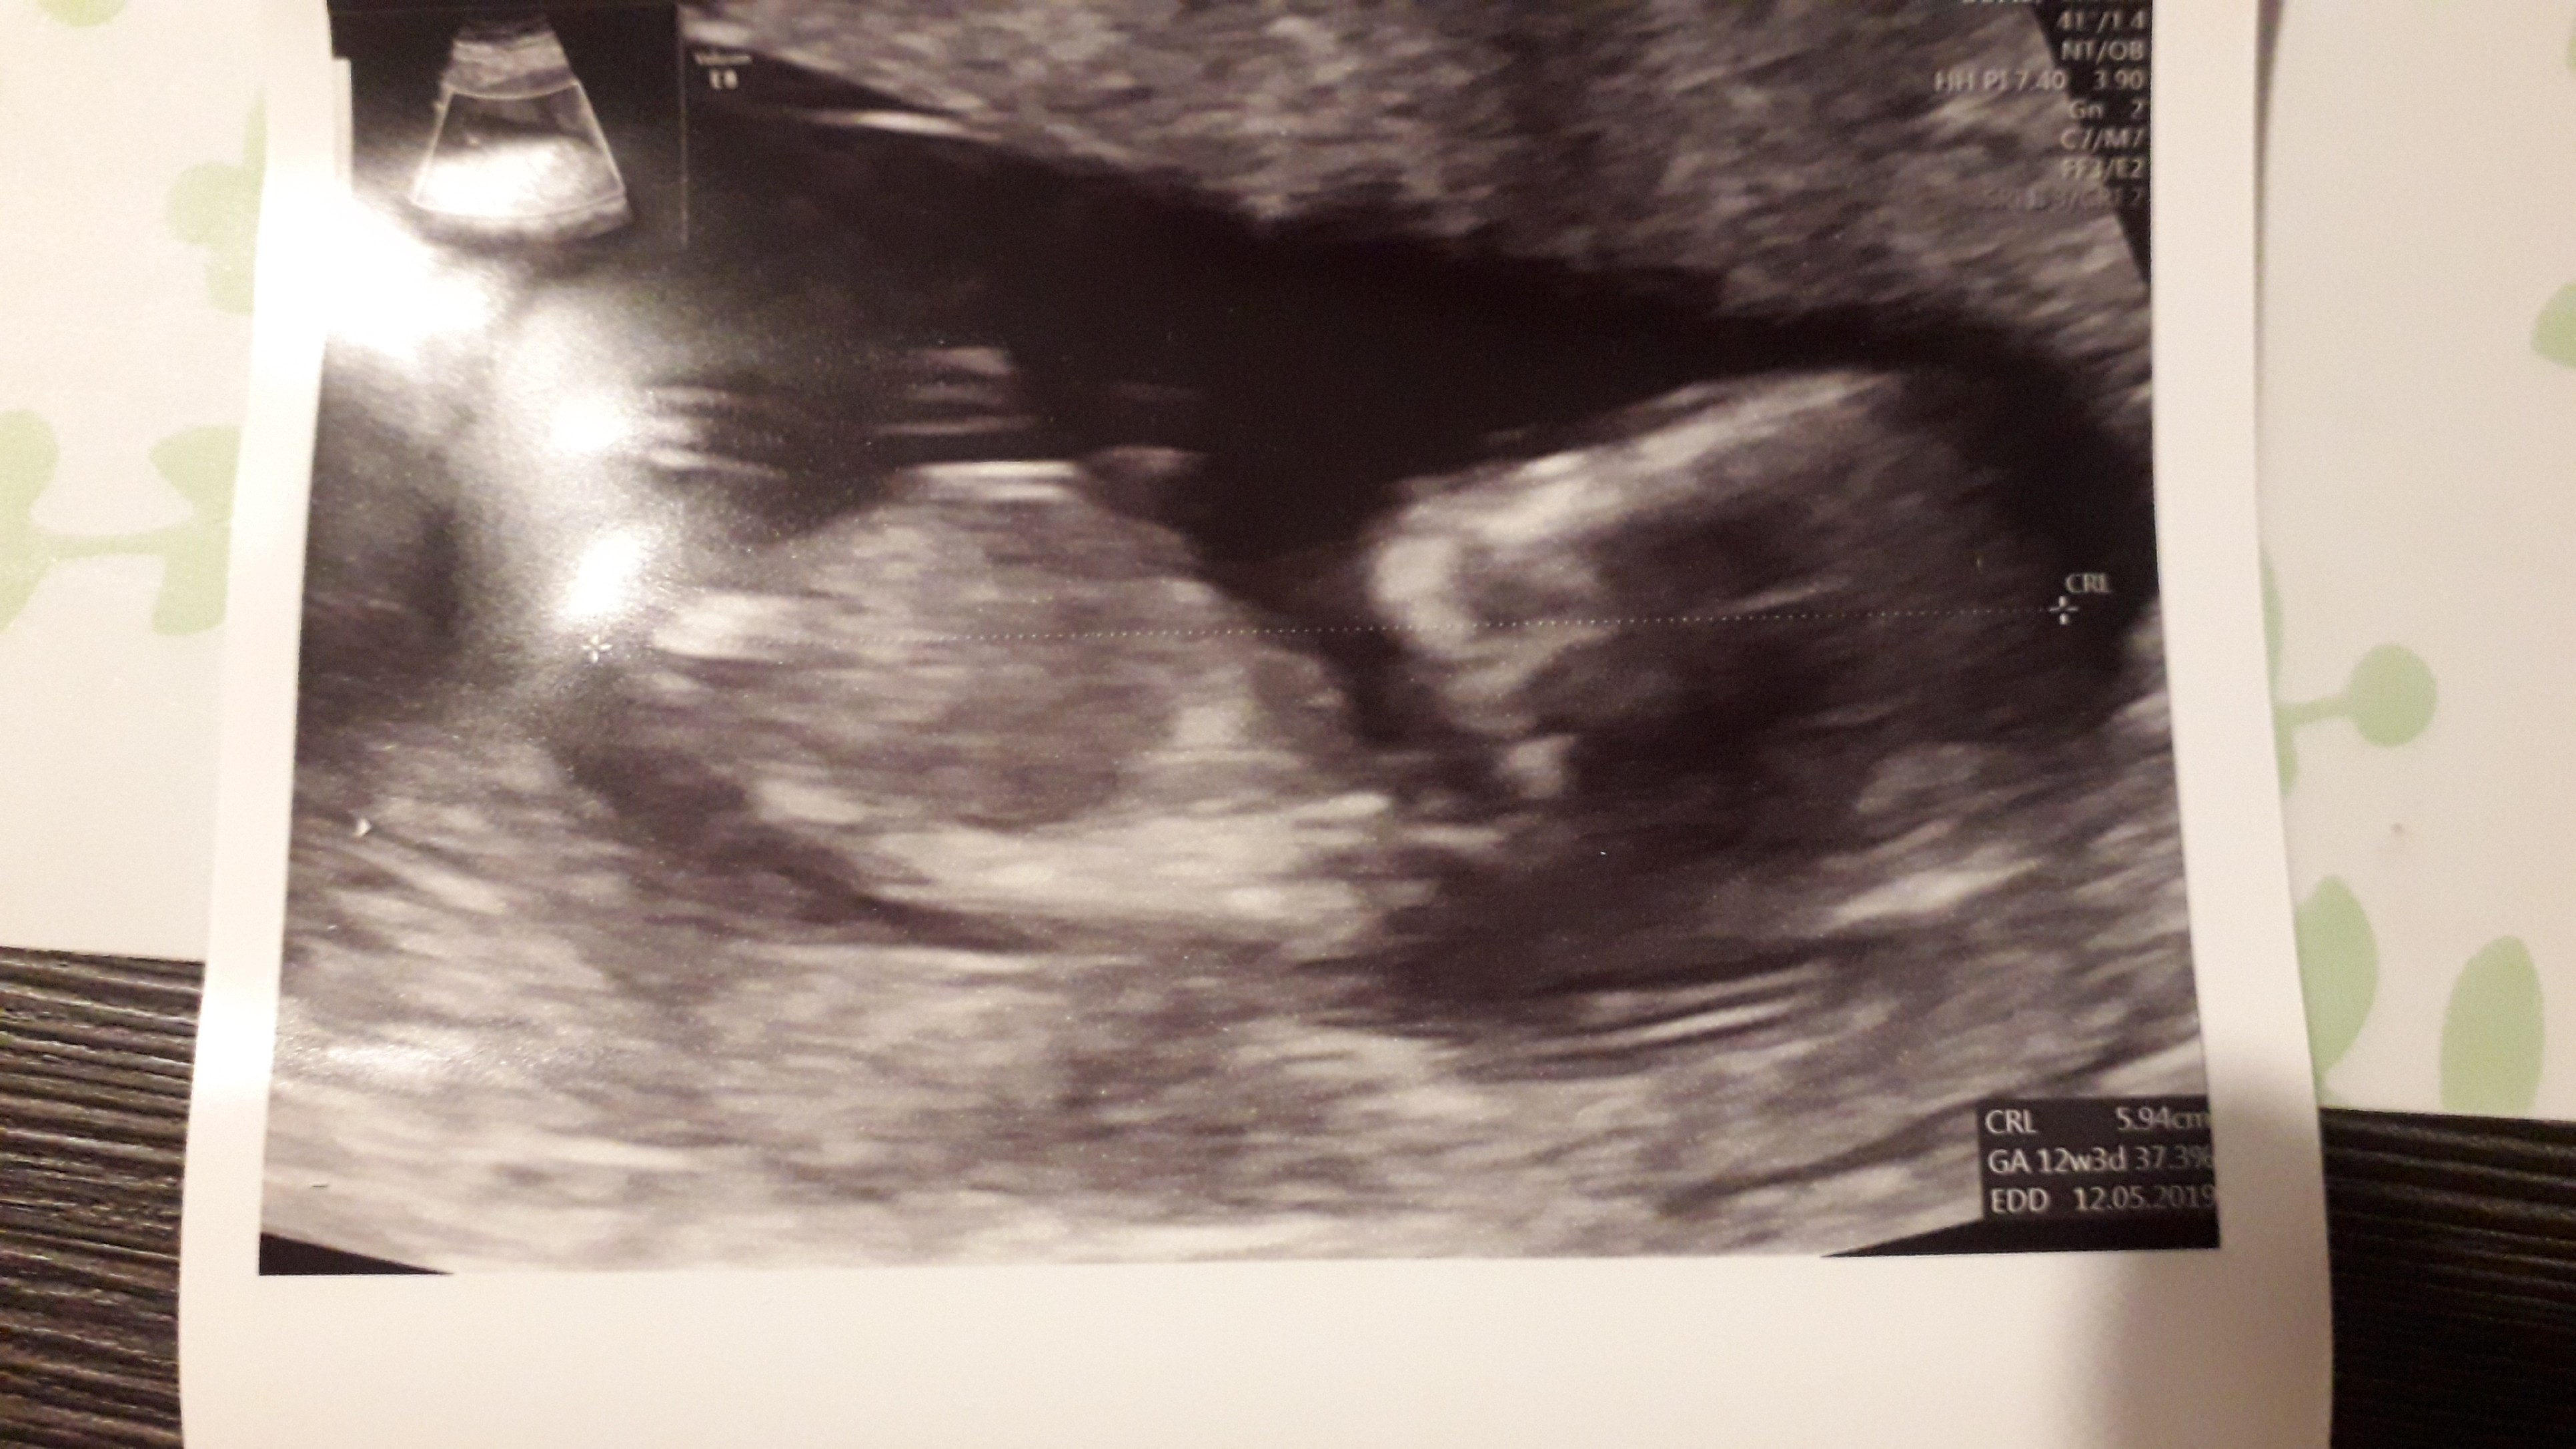

No i jest moja fasola[emoji7]

Na 80% będzie chłopczyk.

20181031_182725.jpg

• 20181031_182725.jpg

29,2 KB · Wyświetleń: 576